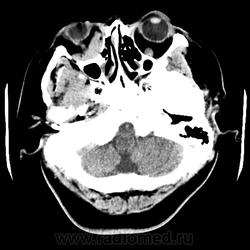

Женщина 48 лет, поступила с подозрением не ОНМК. На КТ -данных за ОНМК не обнаружено, но в правой орбите ретробульбарно мягкотканное образование +45HU, признаков деструкции и ремоделирования костных структур орбиты не наблюдается, медиальная и нижняя прямая мышца отчетливо не дифференцируются, зрительный нерв тесно прилежит к данному образованию. После КУ гомогенное накопление КВ и повышение плотности до +65HU. Экзофтальм. Жалобы на снижение зрения. Год назад делала МРТ ГМ, на снимке патологии орбит не увидел. Идиопатическая псевдоопухоль орбиты?

В мягких тканях носогубного треугольника справа тоже образование.

Натив